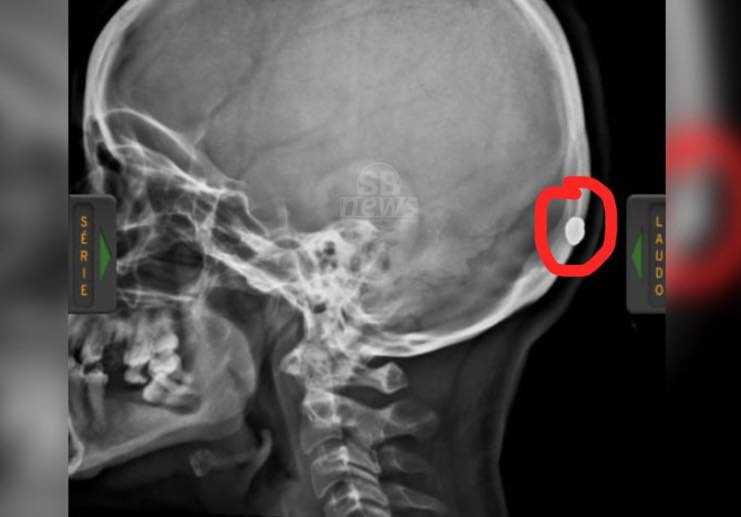

Uma imagem de raio-x mostra o projétil alojado na base do crânio antes da extração. A última informação obtida pela reportagem é de que o estado de saúde da vítima é estável.